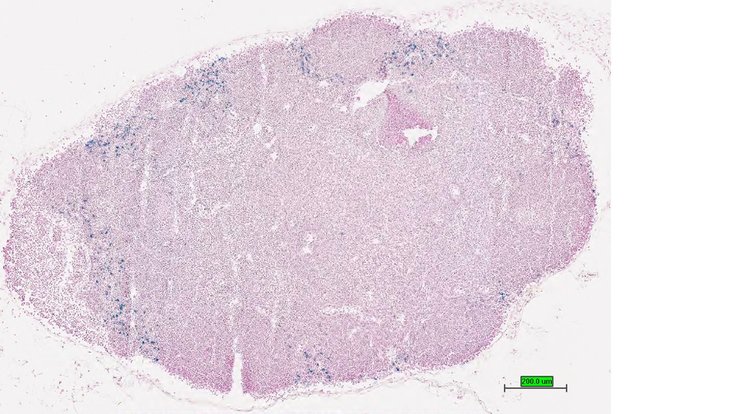

TS28: spleen Present UC Davis_1876327

Specimen UC Davis_1876328: postnatal adult; Ccr6tm1.1(KOMP)Vlcg/Ccr6+ (more )

Structure Level Pattern Image Note

TS28: spleen Present UC Davis_1876328